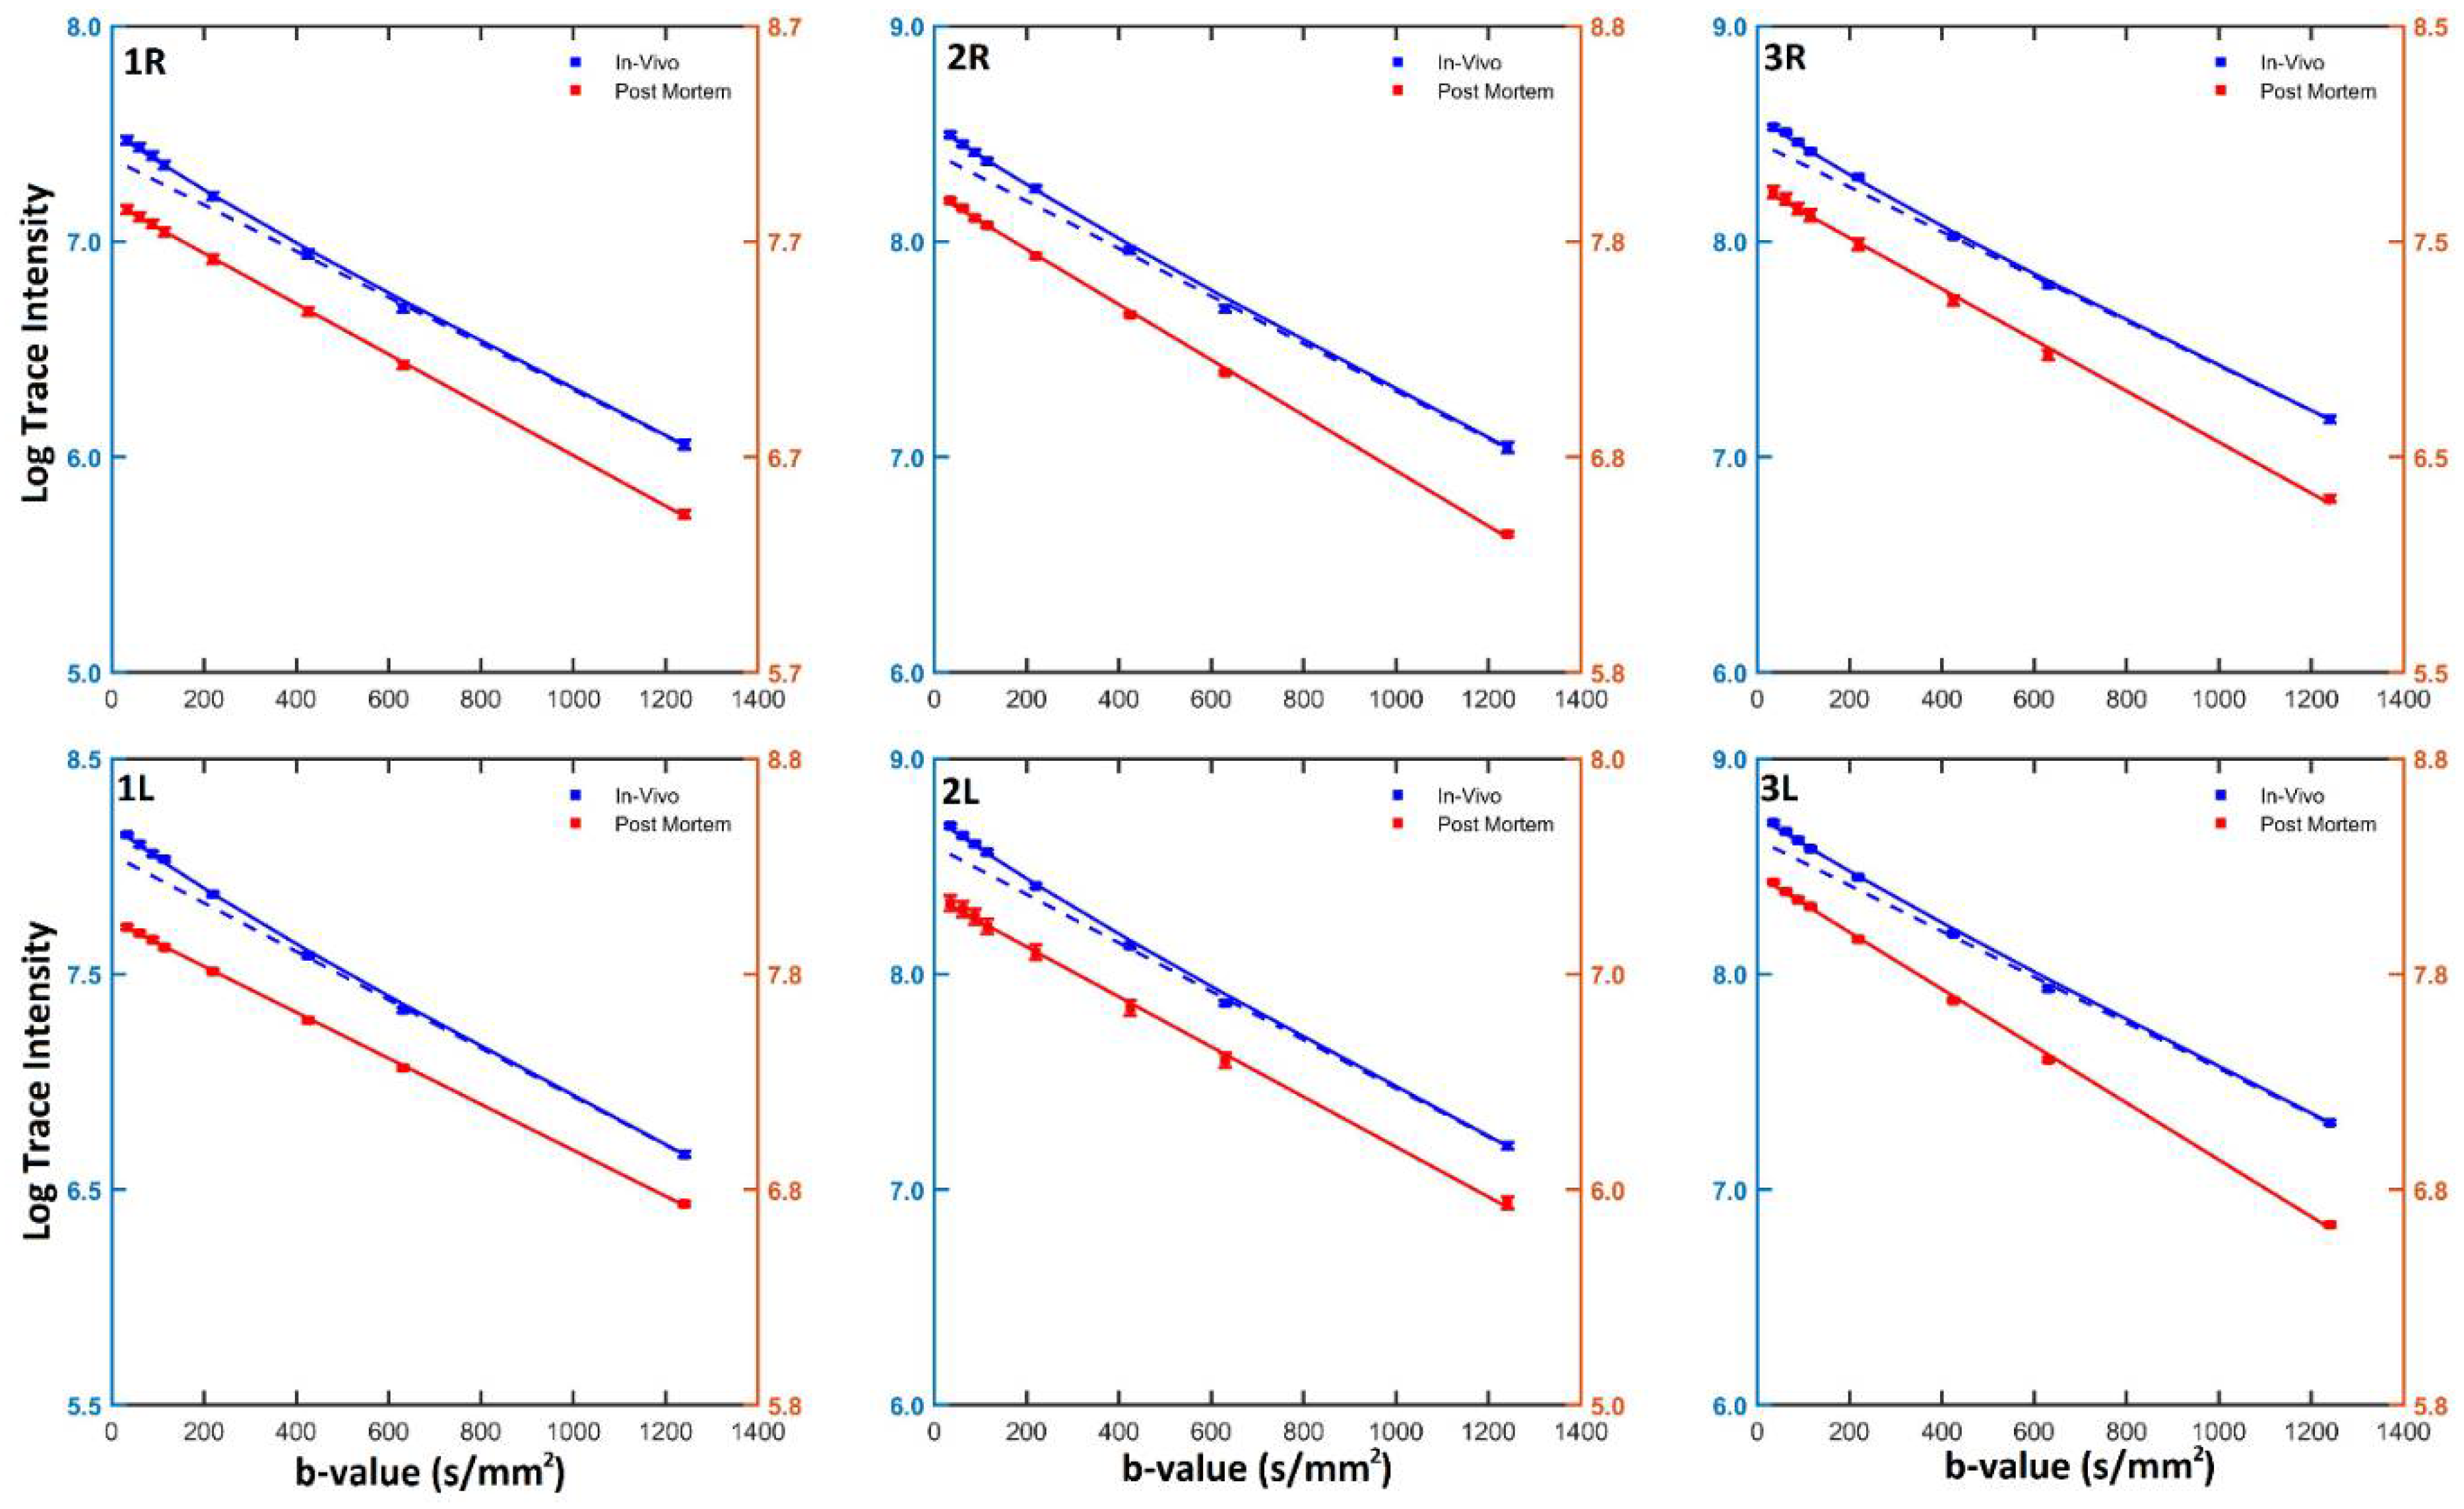

2.2. Data Analysis

3. Results